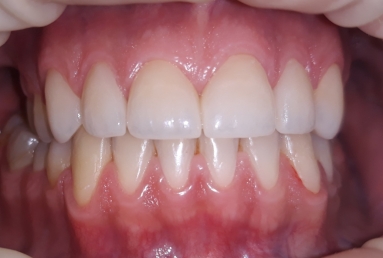

The final porcelain veneers for all frontal maxillary teeth are completed with tooth whitening and changing some composite fillings in lower frontals. On the lower left side a dental implant is inserted, on the upper right side external sinus lift is done. the treatment will be finalised with another upper implant, then two crowns on implants.